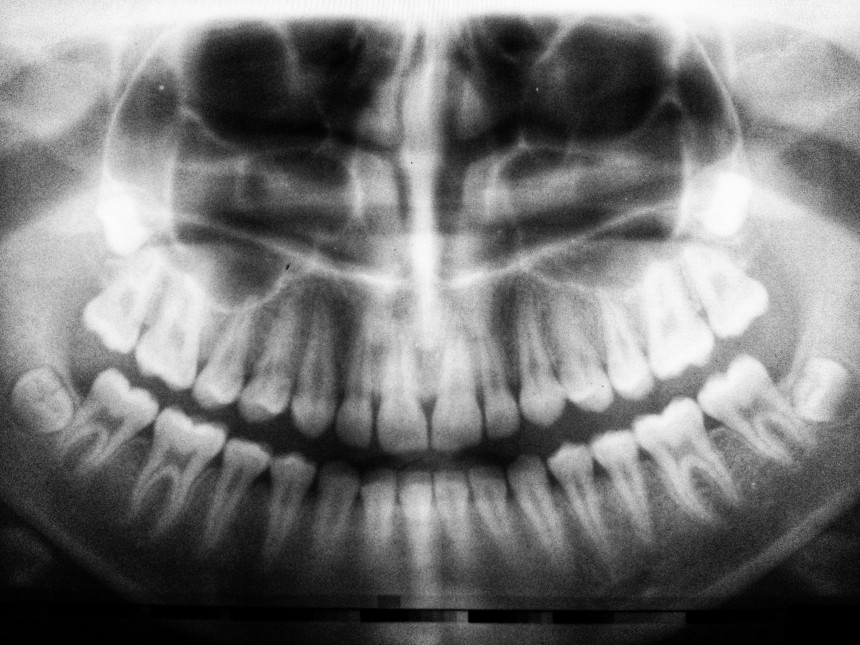

Atšķirībā no rāpuļiem un zivīm, kas regulāri nomaina ilkņus, ir plaši atzīts, ka cilvēkiem un lielākajai daļai citu zīdītāju dzīves laikā izaug tikai divi zobu komplekti.

Bet zem mūsu smaganām ir paslēpti vēl trešās paaudzes snaudoši pumpuri, apgalvo Katsu Takahaši, Osakas Medicīnas pētniecības institūta Kitano slimnīcas mutes ķirurģijas nodaļas vadītājs.

Pārbaudes ar pelēm un seskiem liecina, ka proteīna, ko sauc par USAG-1, bloķēšana var pamodināt trešo kopu, un pētnieki ir publicējuši laboratorijas fotogrāfijas ar ataugušiem dzīvnieku zobiem.

Pagājušajā gadā publicētajā pētījumā komanda teica, ka viņu "antivielu ārstēšana pelēm ir efektīva zobu atjaunošanai un var būt izrāviens zobu anomāliju ārstēšanā cilvēkiem".